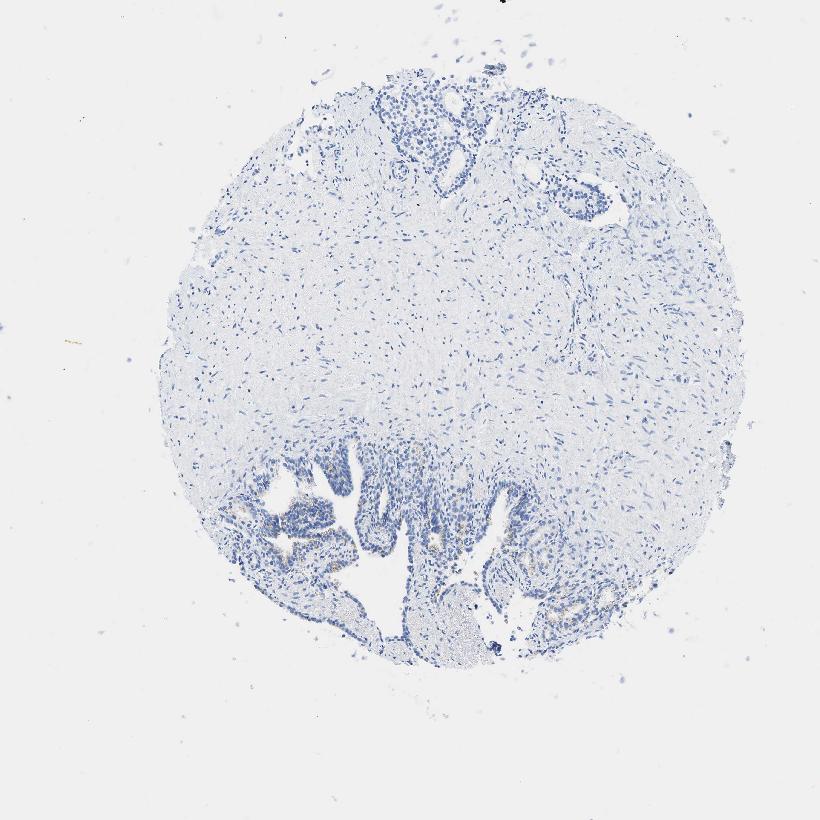

SEMINAL VESICLE - Antibody stainingi

Antibody staining in the annotated cell types in the current human tissue is reported as not detected, low, medium, or high, based on conventional immunohistochemistry profiling in selected tissues. This score is based on the combination of the staining intensity and fraction of stained cells.

Each image is clickable and will lead to virtual microscopy that enables deeper exploration of all samples and also displays staining intensity scores, fraction scores and subcellular localization as well as patient and tissue information for each sample.

Antibody HPA019141Antibody CAB000047

Glandular cells Not detectedNot detected